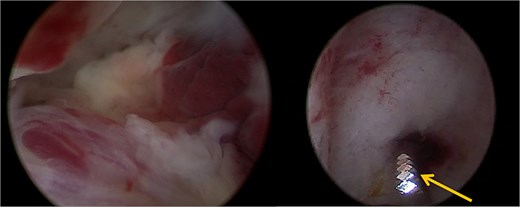

Doppler and 3D-pelvic ultrasound revealed a 12 × 9 mm vascularized intrauterine mass with a Doppler color score of 4, with no signs of myometrial invasion (Fig. 1). Two treatment options were proposed to the patient: initiation of single agent chemotherapy with methotrexate or surgical removal of the retained uterine tissue using a mechanical hysteroscopic tissue removal system.

Intra-uterine vascularized mass (arrows) diagnosed by Doppler (a) and 3D-pelvic (b) ultrasound. The Doppler color score is 4 and there is no suspicion of myometrial invasion (continuous halo surrounding the lesion).